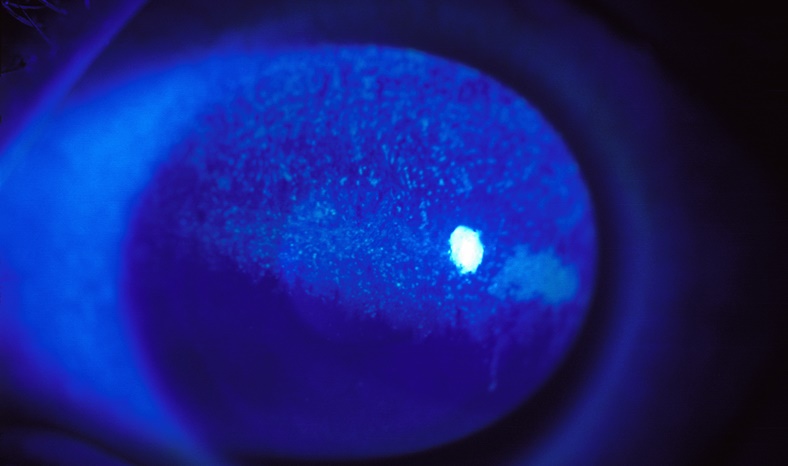

아벨리노 각막이상증(Avelino corneal dystrophy)은 각막에 상처가 났다가 회복하는 과정에서 각막이 혼탁해지고, 시력 저하를 유발하는 유전성 질환입니다. 이 유전자를 가진 사람은 레이저로 각막을 절삭할 경우 각막 혼탁이 급격히 진행될 수 있어 레이저 시력교정술은 금기입니다.